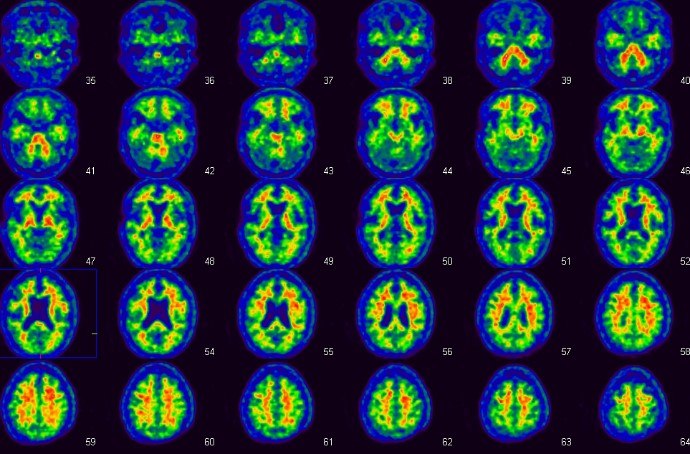

この検査は、アルツハイマー型認知症の代表的病理像である脳内のアミロイドβ蛋白の蓄積状態を画像化した画期的な検査で、当院では治験や臨床研究として行われています。アミロイドβ蛋白蓄積のある物忘れや軽度認知障害の方などは、今後アルツハイマー型認知症に進行する可能性があるため、発症前・早期診断や鑑別診断に有効と考えられています。

アルツハイマー型認知症 健常人